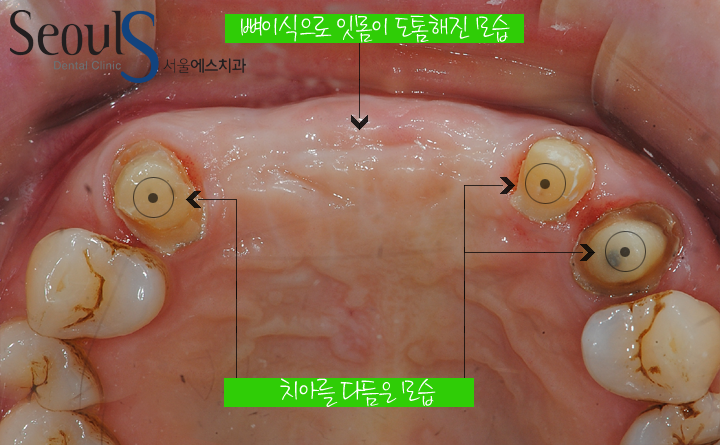

임플란트 식립 후 잇몸이 아문 모습입니다

뼈이식 후 잇몸이 도톰해진 모습을 확인 할 수 있습니다

그리고 크라운 치료를 위해 각각의 치아를 다듬은 모습입니다

뼈이식 전후 잇몸 모습입니다

치아가 빠진 후 잇몸이 점점 흡수되서 들어가 갔는데

뼈이식+임플란트 식립 후 잇몸이 도톰해진 모습입니다